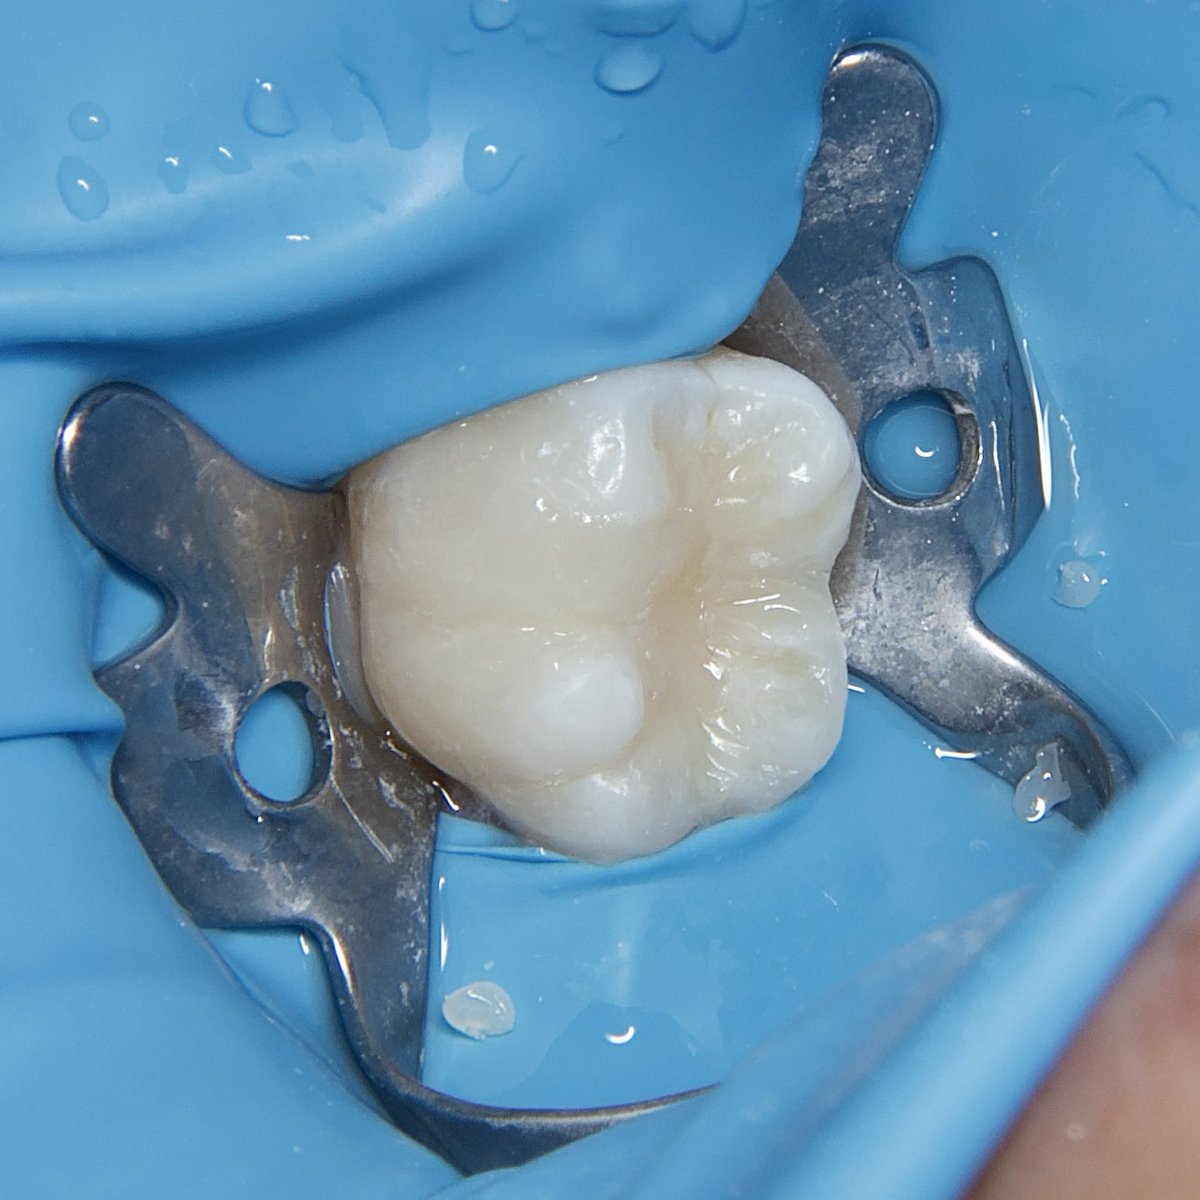

E-max Endocrown for #36 😍🤍 All procedure done under rubber dam IDS , surface treatments and cementation تلبسية جزئية من مادة الخزف للحفاظ على الضرس بعد علاج العصب 🦷

E-max Endocrown for #36 😍🤍

All procedure done under rubber dam

IDS , surface treatments and cementation

تلبسية جزئية من مادة الخزف للحفاظ على الضرس بعد علاج العصب 🦷